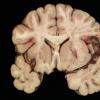

Meningitis

Meningitis, acute (2)